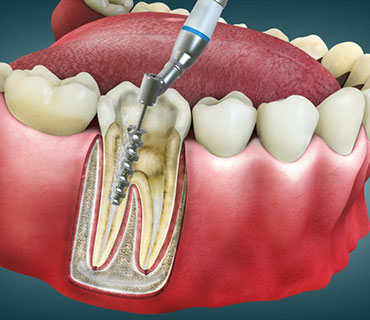

علاج قناة الجذر بدون ألم

يمكن علاج قناة الجذر بدون ألم باستخدام تقنيات طب الأسنان الحديثة والرعاية المناسبة للمريض.

- استشارة ما قبل العلاج

- التاريخ الطبي

- الأدوات الدوارة

- التصوير الرقمي